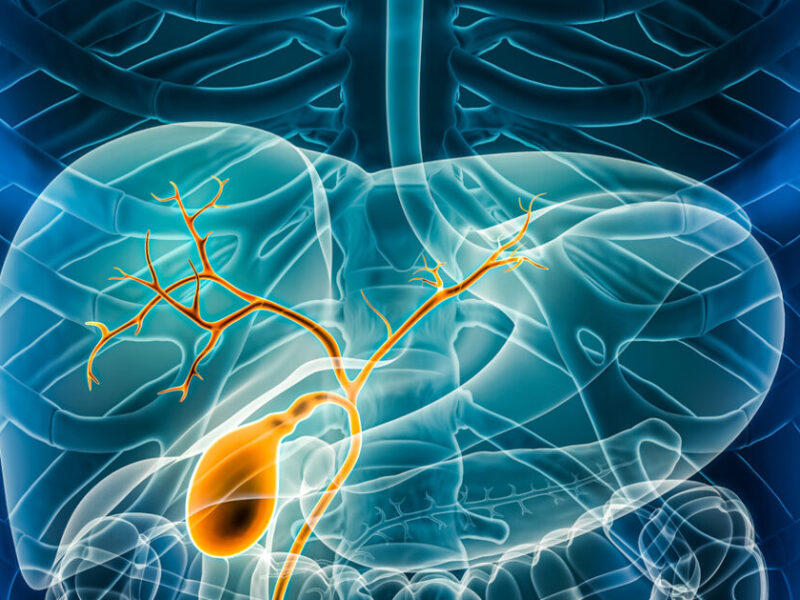

Η χοληδόχος κύστη είναι ένα μικρό όργανο που βρίσκεται κάτω από το ήπαρ, στο δεξιό άνω τμήμα της κοιλιάς.

Ο ρόλος της είναι να αποθηκεύει τη χολή, μια ουσία που παράγεται από το ήπαρ και φυλάσσεται εκεί μέχρι να απελευθερωθεί στο δωδεκαδάκτυλο, όπου συμβάλλει στην πέψη των τροφών, ιδιαίτερα όσων περιέχουν λιπαρά.